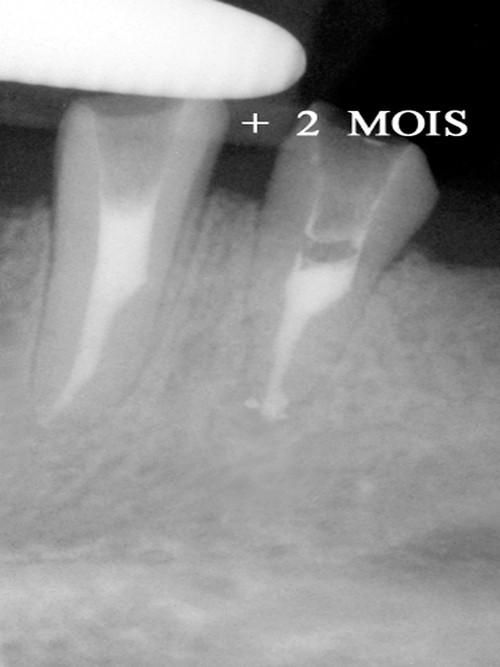

Infection péri apicale sur les deux piliers de bridge

Le chirurgien dentiste utilise un rayonnement laser pénétrant transporté par une fibre optique qui permet d’éviter toute chirurgie en décontaminant les tissus osseux voisins de la racine par la voie endo canalaire (fig.16).

fig. 16

La fibre optique transporte le rayonnement laser au bout des racines